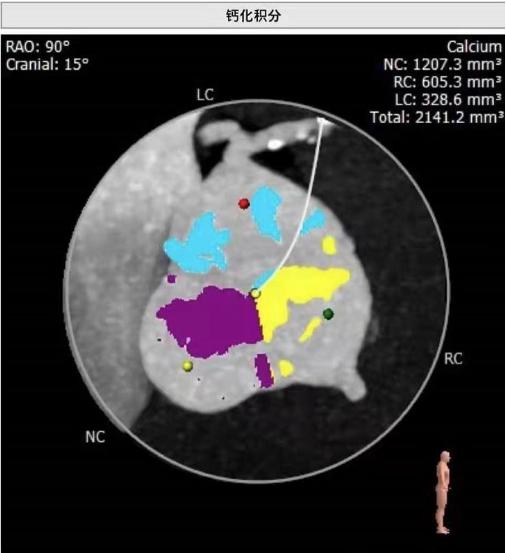

心内科主任医师何晋发现杨爷爷心脏杂音很重,怀疑心脏瓣膜出了问题,经心脏超声检查,果不其然,杨爷爷的心脏有个大“BUG”——主动脉瓣重度狭窄伴中度关闭不全,也就是心脏的阀门坏了,导致他主动脉瓣上下的压差高达70mmHg,而严重的瓣膜病变引发了心脏肥厚、心功能受损,检查还发现他的冠状动脉病变也很严重。

杨爷爷年龄大、心功能差,不能接受外科手术,但如果保守治疗,这类患者的两年生存率不到50%。综合考虑下,何晋主任医师团队多次讨论,最终为杨爷爷制定了经导管主动脉瓣置换及冠脉支架(TAVI+PCI)手术方案,不需要开胸,降低了手术风险。经过精心术前准备,何晋主任医师团队联合心外科、体外循环、麻醉科、介入手术部等多学科,为杨爷爷完成了高难度、超高龄的经导管主动脉瓣置换联合冠脉介入术。

术中,在DSA(数字减影血管造影)严密实时监测下,何晋主任医师从杨爷爷大腿根部股动脉穿刺,通过大血管将主动脉支架瓣膜及装置输送到病变的主动脉瓣位置,缓缓释放支架瓣膜,经过精密调控,支架瓣膜精确植入,原先狭窄的瓣膜口子一下就开通了,术中监测主动脉瓣和心室压差为零。